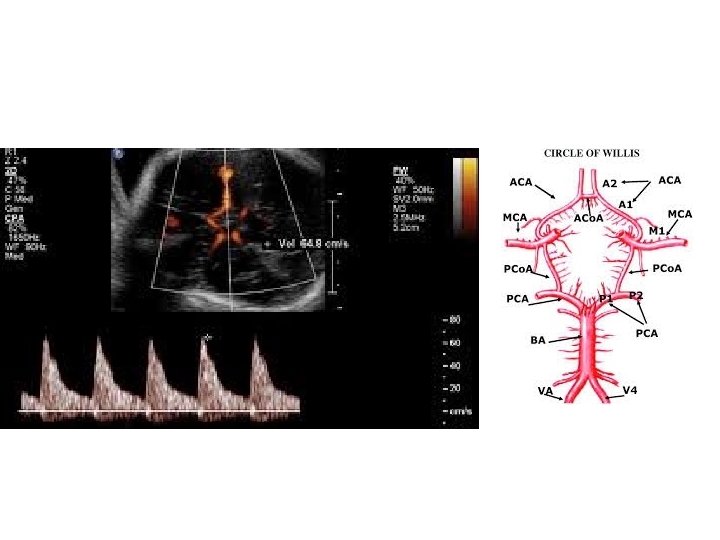

Obstetrik Doppler Ultrasonografi • Umblikal arter Doppler’i en yaygın olarak kullanılan fetal Doppler değerlendirmesidir ve en fazla kullanılan Doppler parametresidir. • Orta serberal arter Doppler • Umblikal arter Doppler değerlendirmesinde direnç artışı, diyastol sonu akımda kayıp veya ters dönme saptanması , artmış perinatal mortalite hızı ile ilişkili olmakla birlikte fetal gelişme geriliği olgularında doğum zamanlamasının belirlenmesini de etkilemektedir.

• Duktus venosus Doppler’inin kötü perinatal sonuçları tahmin etmedeki katkısı sınırlı olmakla birlikte yenidoğan sonuçlarını öngörmede en önemli kardiyovasküler parametre duktus venosus Doppler’idir.

Eğer akım transdu sere doğru ise, yol uzunluğu kısadır ve geri dönen frekans yu ksektir. Eğer akım transdu serden uzaklaşıyorsa, yol uzar ve geri dönen frekans azalır.